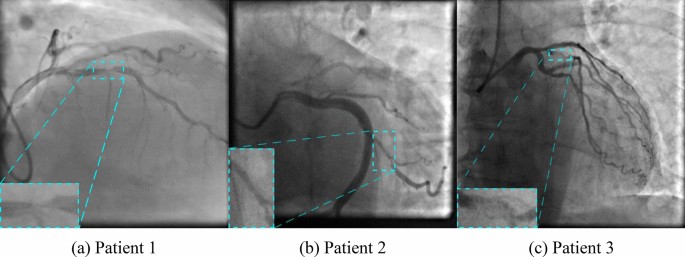

Angiographic images of the radiopaque overlaid coronary arteries with stenotic segments were selected and converted into separate images. An interventional cardiologist rejected non-informative images and selected only those containing contrast passage through a stenotic vessel. A total of 8325 grayscale images (100 patients) of 512 × 512 to 1000 × 1000 pixels were included for further study. Of them, 6660 (80%), 833 (10%), and 832 (10%) images were used for training, validation, and testing respectively. In order to correctly estimate model performance, we did not randomly shuffle all 8325 images and then form data subsets. We first randomly choose patient series for the training, validation, and testing subsets in an 80:10:10 ratio, and then form those subsets. Such data split allows us to know that the validation and testing are done on the independent subsets of images and avoid bias in performance metrics. Since the training process is quite time-consuming, we excluded the usage of cross-validation for the models. Data were labeled using the LabelBox, a free version of SaaS (Software as a Service). It allows joint data labeling and subsequent validation by several specialists. Typical data labeling of the source images is shown in Fig. 1.

The capabilities of the selected neural networks are presented using the data of three patients with the referenced labeling (Fig. 9a–c). Detailed visualization for predictions is presented in Online Appendices H–J. The models with the best values of the loss function and mAP were used for testing.

Almost all models may accurately detect the location of stenosis. However, we faced several false positives while testing the Faster-RCNN NASNet model. In all three cases, this model detected the location of false stenotic segments with a probability of more than 90% in the right coronary artery (Fig. 9d) and the anterior descending artery (Fig. 9e, f) besides the reference stenotic region. SSD MobileNet V1 and SSD ResNet-50 V1 models failed to detect the location of stenosis in patient 1. SSD MobileNet V2 model demonstrated one of the best results in predicting the location of stenosis (Fig. 10). Despite the DSC metric of 0.65 in patient 3, it had the highest DSC metric in patients 1 and 2 (0.93 and 0.98, respectively). Additionally, the detectors based on the ResNet architecture, Faster-RCNN ResNet-50 V1 and Faster-RCNN ResNet-101 V2, should be noted. The average DSC metric on the test data was 0.85 and 0.84, respectively.